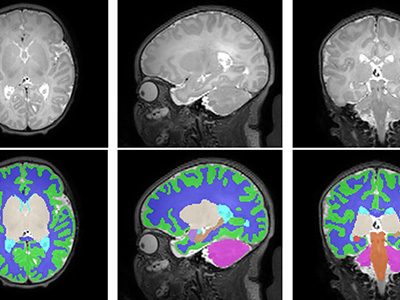

In a study involving 173 newborns who were exposed to opioids during pregnancy and 96 newborns not exposed to opioids prenatally showed smaller brain sizes in several key areas. Specifically, these exposed babies had smaller total brain volumes, as shown through MRI, as well as reduced volumes in important parts of the brain, including the cortex (outer layer of the brain), deep gray matter (areas that control movement and emotions), white matter (which helps transmit signals in the brain), cerebellum (responsible for coordination and movement), brainstem (controls basic functions like breathing), and the amygdala (involved in emotions and memory).

Further details showed that newborns exposed to medication for opioid use disorder (MOUD) during pregnancy with methadone, had smaller white matter volumes, while those exposed to MOUD with buprenorphine had smaller volumes specifically in the right amygdala. Additionally, newborns who were exposed to opioids plus additional substances such as THC and gabapentin had smaller volumes in even more brain areas compared to those who were only exposed to opioids.